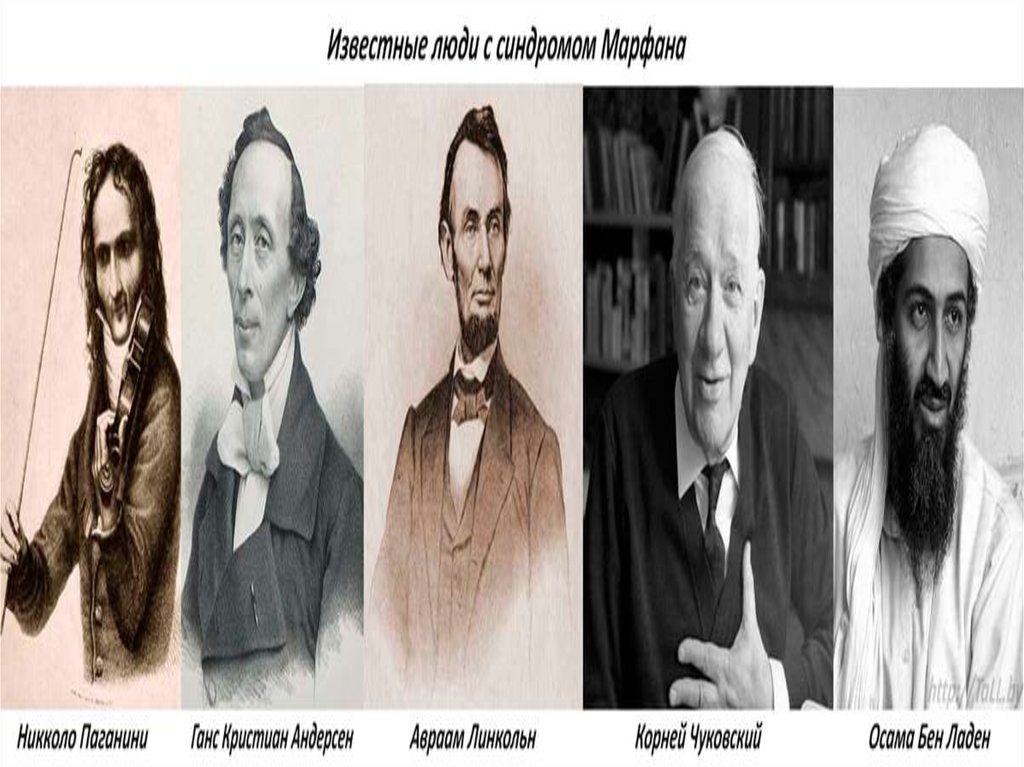

Boleznennyj dar nikkolo paganini redkij sindrom marfana priznaki sposoby lecheniya i nasledovanie u detej sindrom marfana kto bolel iz znamenitostej (Тип файлу jpg)

Boleznennyj Dar Nikkolo Paganini Redkij Sindrom Marfana Priznaki Sposoby Lecheniya I Nasledovanie U Detej Sindrom Marfana Kto Bolel Iz Znamenitostej

Chelovek i ego zdorove sindrom marfana sekrety andersena paganini i chukovskogo obsuzhdenie na liveinternet rossijskij servis onlajn dnevnikov (Тип файлу jpg)

Chelovek I Ego Zdorove Sindrom Marfana Sekrety Andersena Paganini I Chukovskogo Obsuzhdenie Na Liveinternet Rossijskij Servis Onlajn Dnevnikov